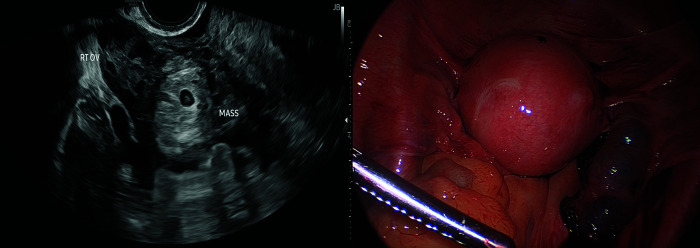

Three cases of atypical ectopic pregnancies requiring surgical evaluation are presented. The first case represents an undiagnosed heterotopic pregnancy who initially presented with a 1st trimester spontaneous abortion and subsequently a ruptured ectopic pregnancy. The second case represents an omental ectopic pregnancy vs an extruded tubal ectopic pregnancy following a salpingectomy requiring omentectomy and appendectomy. The third case showcases a chronic cornual ectopic pregnancy incidentally found during a robotic myomectomy. These cases highlight uncommon presentations of atypical ectopic pregnancies, diagnostic challenges, and surgical treatment.